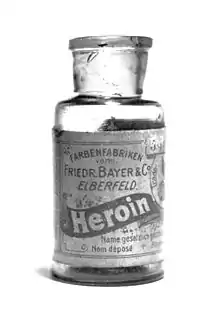

Common forms of rehabilitation include psychotherapy, support groups and pharmacotherapy, which uses psychoactive substances to reduce cravings and physiological withdrawal symptoms while a user is going through detox. Methadone, itself an opioid and a psychoactive substance, is a common treatment for heroin addiction, as is another opioid, buprenorphine. Recent research on addiction has shown some promise in using psychedelics such as ibogaine to treat and even cure drug addictions, although this has yet to become a widely accepted practice.[69][70]